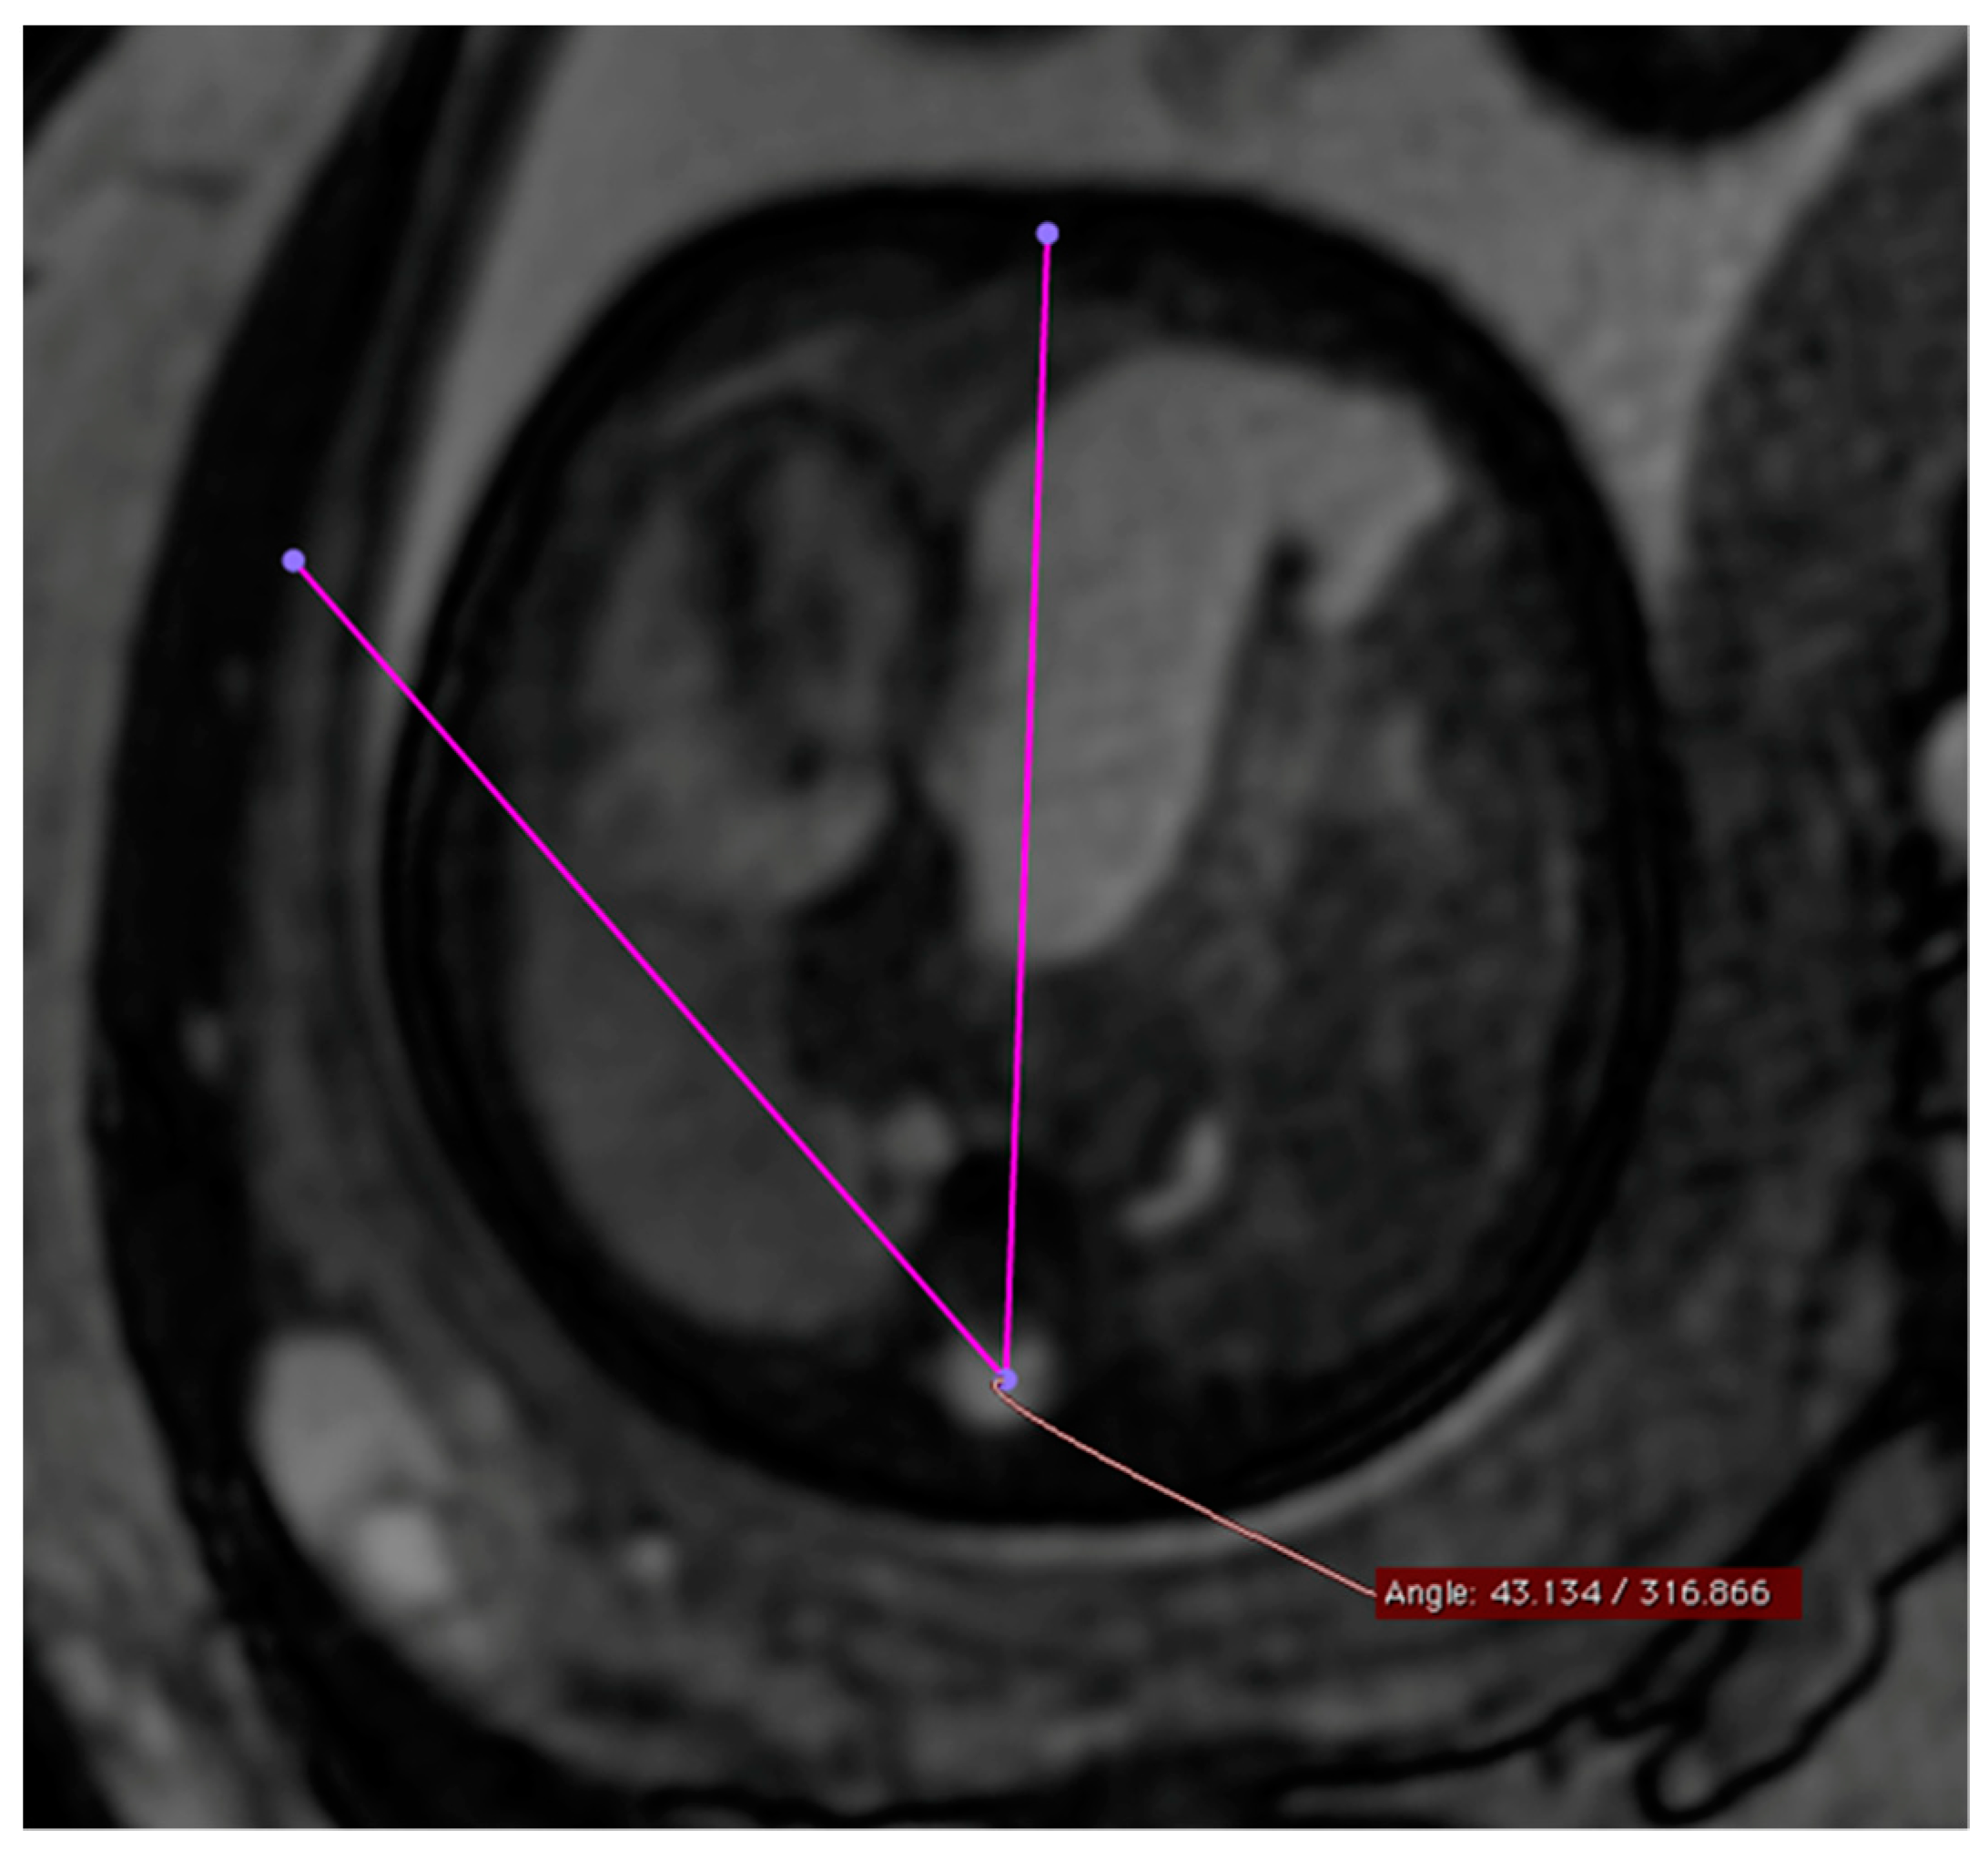

The MSA was quantified using a T2-weighted steady-state sequence (“True fast imaging with steady-state free-precision”—TRUFI) in the transverse section of the fetus in the four-chamber view. The selection of the TRUFI sequence resulted from its ability to clearly delineate the heart from the adjacent lung parenchyma. The use of the four-chamber view as a reference plane ensured easy reproducibility of the angle measurement (Figure 1). To perform the actual angle measurement, a straight line was drawn from the center of the sternum to the center of the spinal canal of the thoracic vertebral body of the same height. A second straight line was drawn from the spinal canal center of the corresponding thoracic vertebral body as a tangent at the outermost point of the pericardial side facing the diaphragmatic defect. The resulting smaller angle α between these two straight lines corresponded to the MSA.

This figure illustrates a T2 steady-state free-precision (TRUFI) sequence in the axial section plane (uniform four-chamber plane) of a fetal MRI scan in a patient with left congenital diaphragmatic hernia (CDH). In this MRI representation, the measurement of the mediastinal shift angle α is visualized as an example.

Figure 1. Measurement of MSA (mediastinal shift angle).